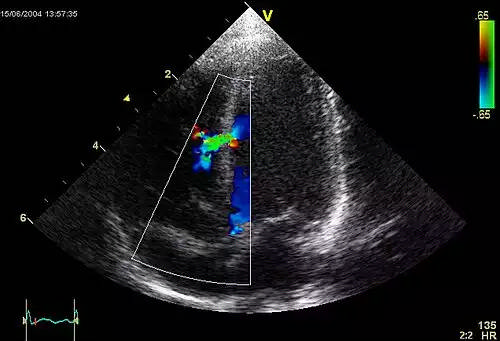

اکوکاردیوگرام نه تنها می تواند تصاویر سونوگرافی از ساختارهای قلب ایجاد کند، بلکه می تواند با استفاده از سونوگرافی داپلر ارزیابی دقیقی از خون جریان یافته به بافت قلب ایجاد کند. داپلر رنگی و همچنین داپلر طیفی برای به نصویر کشیدن هرگونه ارتباط غیر عادی بین دو طرف چپ و راست قلب، نشتی خون از طریق دریچه ها ( نارسایی دریچه ای ) و تخمین میزان باز بودن دریچه ها ( یا باز نشدن آنها ) استفاده می شود.